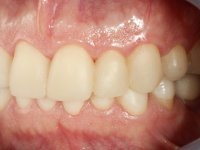

Após análise clínica e imagiológica foi proposto ao paciente recuperar a dimensão vertical da oclusão essencialmente à custa de incrementos oclusais inferiores utilizando “overlays” no sector posterior e facetas no sector anterior. A coroa aparafusada sobre o implante 3.5 seria substituída, no sentido de acompanhar este incremento. Na maxila o dente 2.6 teria extração indicada e posteriormente seria reabilitado com um implante e respetiva coroa. No sentido de reabilitar esteticamente o paciente duma forma minimamente invasiva, foi proposta a colocação de facetas feldespáticas no sector antero-superior. O objetivo de aumentar ligeiramente a D.V.O., teria como função “proteger” eficazmente o sector antero-superior.

Realizado o diagnóstico e tomada a decisão quanto ao tratamento a executar, tornou-se importante definir qual a sequência de trabalho a adotar no sentido de conseguir a reabilitação da D.V.O. (V.D.O), de forma progressiva e equilibrada. Na primeira fase fez-se uma pré-impressão da arcada inferior com silicone tipo “putty” e em seguida realizou-se o preparo dentário de todo o sector posterior. O preparo para os overlays foi feito coronalmente à linha amelo cementaria no sentido de ser o mais conservador possível. A impressão foi feita com técnica de dupla mistura após afastamento gengival realizado com pasta de caulino. A provisória foi realizada com resina composta de polimerização dual. Em laboratório foram realizados os overlays após se ter aberto ligeiramente (1,5mm) a D.V.O. nos modelos montados em articulador semi-ajustável. Simultaneamente o sector antero-inferior foi encerado no sentido de acompanhar este aumento da D.V.O. Também foi confecionada uma chave de silicone translucido para posterior confeção dos provisórios antero-inferiores. Em boca foi primeiro realizada a provisionalização dos dentes anteriores utilizando resina composta previamente aquecida após preparação das superfícies dentárias para a adesão. Foi colocado o dique de borracha para promover o isolamento absoluto e posteriormente foram colados os overlays. Em laboratório foi realizada nova chave de silicone para confecionar os provisórios antero-superiores. Seguidamente em boca foram preparados os seis dentes antero-superiores após colocação do fio de afastamento gengival. Feita a preparação adequada das superfícies dentárias foi realizada a impressão com técnica de dupla mistura e a respetiva provisória. Em laboratório foram confecionadas 6 facetas feldespáticas num modelo de trabalho tipo “Geller”. A provisória foi removida e as facetas foram coladas em boca utilizando um isolamento relativo competente. Esta opção foi tomada em virtude de uma prévia experiencia negativa com a colocação do dique de borracha na mandibula. Após a colagem dos laminados antero-superiores foram dadas 12 semanas para avaliar a adaptação do paciente à nova situação e então iniciar a confeção das facetas antero-inferiores. Após colocação do fio de afastamento gengival. foram feitos os preparos dentários adequados e em seguida foi feita a impressão. Também foi feita a preparação do dente 3.4 que, entretanto, tinha sofrido uma fratura do overlay. As facetas e a restauração do 3.4 foram realizadas num modelo de trabalho tipo “Geller”. Após remoção da provisória, as facetas foram coladas em boca, utilizando um isolamento relativo pelas razões apontadas anteriormente. Após colocação do trabalho o paciente foi reabilitado por outros colegas com um implante na zona do 2.6 e substituição da coroa aparafusada sobre o implante colocado no local do 3.5. Posteriormente surgiram fraturas nos overlays dos dentes 4.7 e 3.7 que foram reabilitados com overlays em Zr.